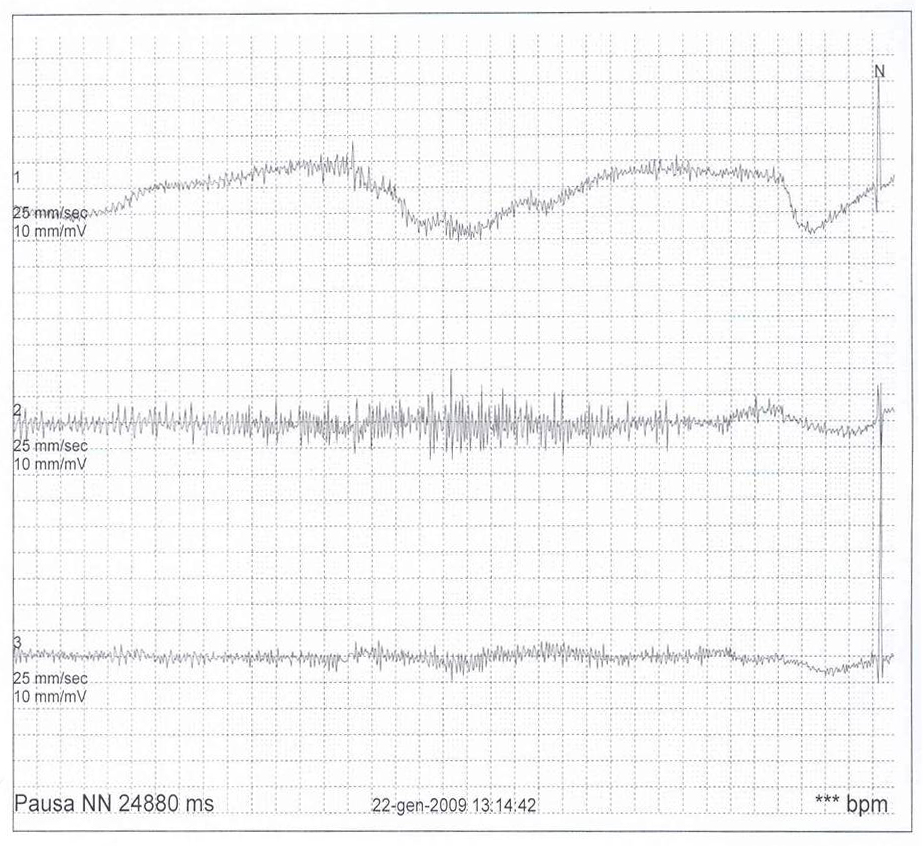

Tale ipotesi � stata poi confermata da un nuovo ECG Holter 24 ore che ha evidenziato, durante uno spasmo affettivo pallido spontaneo esitato in sincope e crisi convulsiva generalizzata, un�asistolia di circa 25 secondi (Figura 1). � stata quindi iniziata terapia vagolitica con atropina solfato per os (0,01 mg/kg/dose per 2 somministrazioni/die) per contrastare l�iperreattivit� parasimpatica ritenuta responsabile dell�asistolia. Questa terapia si � rivelata inefficace. La bambina ha infatto presentato alcune recidive di spasmo respiratorio pallido, sincope e crisi convulsiva. Vista la sua particolarit�, il caso � stato discusso su un forum di cardiologia pediatrica accessibile in rete (Pediheartnet) da cui sono emersi sostanzialmente due progetti terapeutici: il primo, di maggioranza, raggruppava i fautori dell�impianto di un pacemaker ventricolare; il secondo, di minoranza, raggruppava i fautori di una terapia farmacologica con diversi farmaci come teofillina, clonidina, sertralina, cerotto di scopolamina, glicopirrolato. Anche alla luce di tali pareri, viste le possibili complicanze relative all�impianto di un pacemaker in un bambino di 10 kg di peso, abbiamo deciso di tentare nuovamente una terapia medica con farmaci anticolinergici; in particolare, tra il cerotto transdermico di scopolamina e il glicopirrolato la scelta � caduta su quest�ultimo (alla dose di 0,5 mg per 3 volte al giorno per os) in quanto meglio dosabile nel siero. Al glicopirrolato abbiamo associato teofillina a rilascio prolungato (80 mg ogni 12 ore per os). Il razionale di questo approccio combinato risiede nella possibilit� di modulare con il glicopirrolato (un anticolinergico ad azione pi� lunga di quella dell�atropina) l�inibizione cardiaca indotta dallo spasmo pallido e nel determinare con la teofillina un effetto cronotropo positivo e una stimolazione del centro del respiro. Dall�inizio del trattamento a oggi (11 mesi di follow-up) la paziente ha continuato a presentare spasmi affettivi non solo di tipo pallido, ma anche di tipo cianotico, senza per� presentare in nessuna occasione sincope o crisi convulsiva.

Figura 1. |